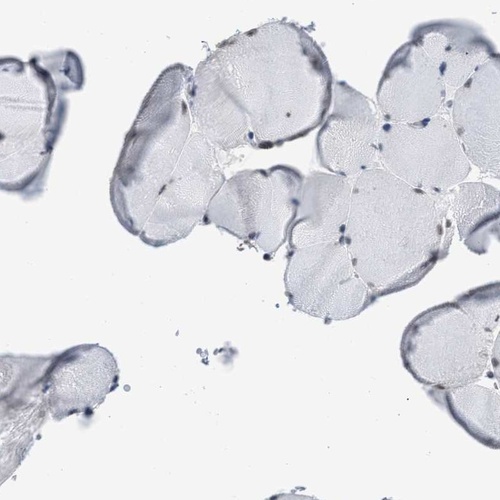

Immunohistochemistry analysis in human testis and skeletal muscle tissues using Anti-SCAF4 antibody. Corresponding SCAF4 RNA-seq data are presented for the same tissues.